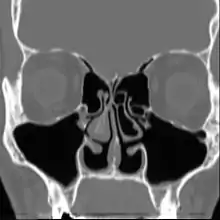

![]() | |

| Altered nasal anatomy after bilateral subtotal inferior turbinectomy, the removal of most turbinate tissue. | |